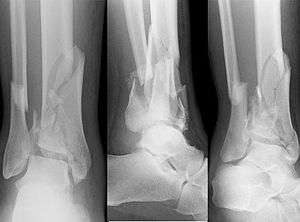

| X-ray of a fracture involving the articular surface of the Tibia | |

A Pilon fracture, also called a Plafond fracture, is a fracture of the distal part of the tibia, involving its articular surface at the ankle joint. Pilon fractures are caused by rotational or axial forces, mostly as a result of falls from a height or motor vehicle accidents. Pilon fractures are rare, comprising 3 to 10 percent of all fractures of the tibia and 1 percent of all lower extremity fractures, but they involve a large part of the weight bearing surface of the Tibia in the ankle joint. Because of this, they may be difficult to fixate and are historically associated with high rates of complications and poor outcome.[1][2][3]